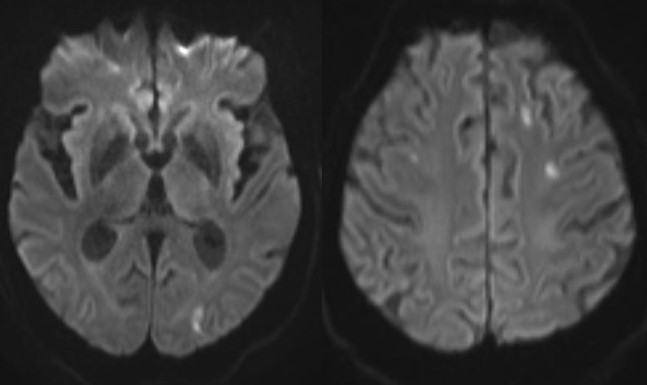

Neurological disease: Approximately 15–20% of hospitalized patients develop altered mental status or more focal symptoms. Imaging is positive in a minority, however. Ischemic infarcts are the most common imaging findings, probably related to coagulopathy. Reported infrequently are hemorrhagic stroke, cranial nerve inflammation, encephalopathy, and worsening of multiple sclerosis plaques.